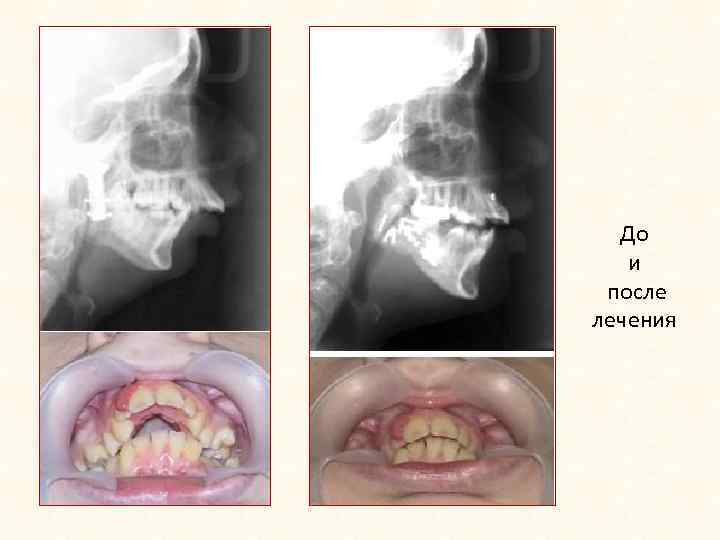

Односторонний деформирующий артроз

До и после лечения